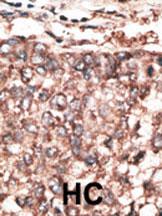

Formalin-fixed and paraffin-embedded human cancer tissue reacted with the primary antibody, which was peroxidase-conjugated to the secondary antibody, followed by AEC staining. This data demonstrates the use of this antibody for immunohistochemistry; clinical relevance has not been evaluated. BC = breast carcinoma; HC = hepatocarcinoma. |